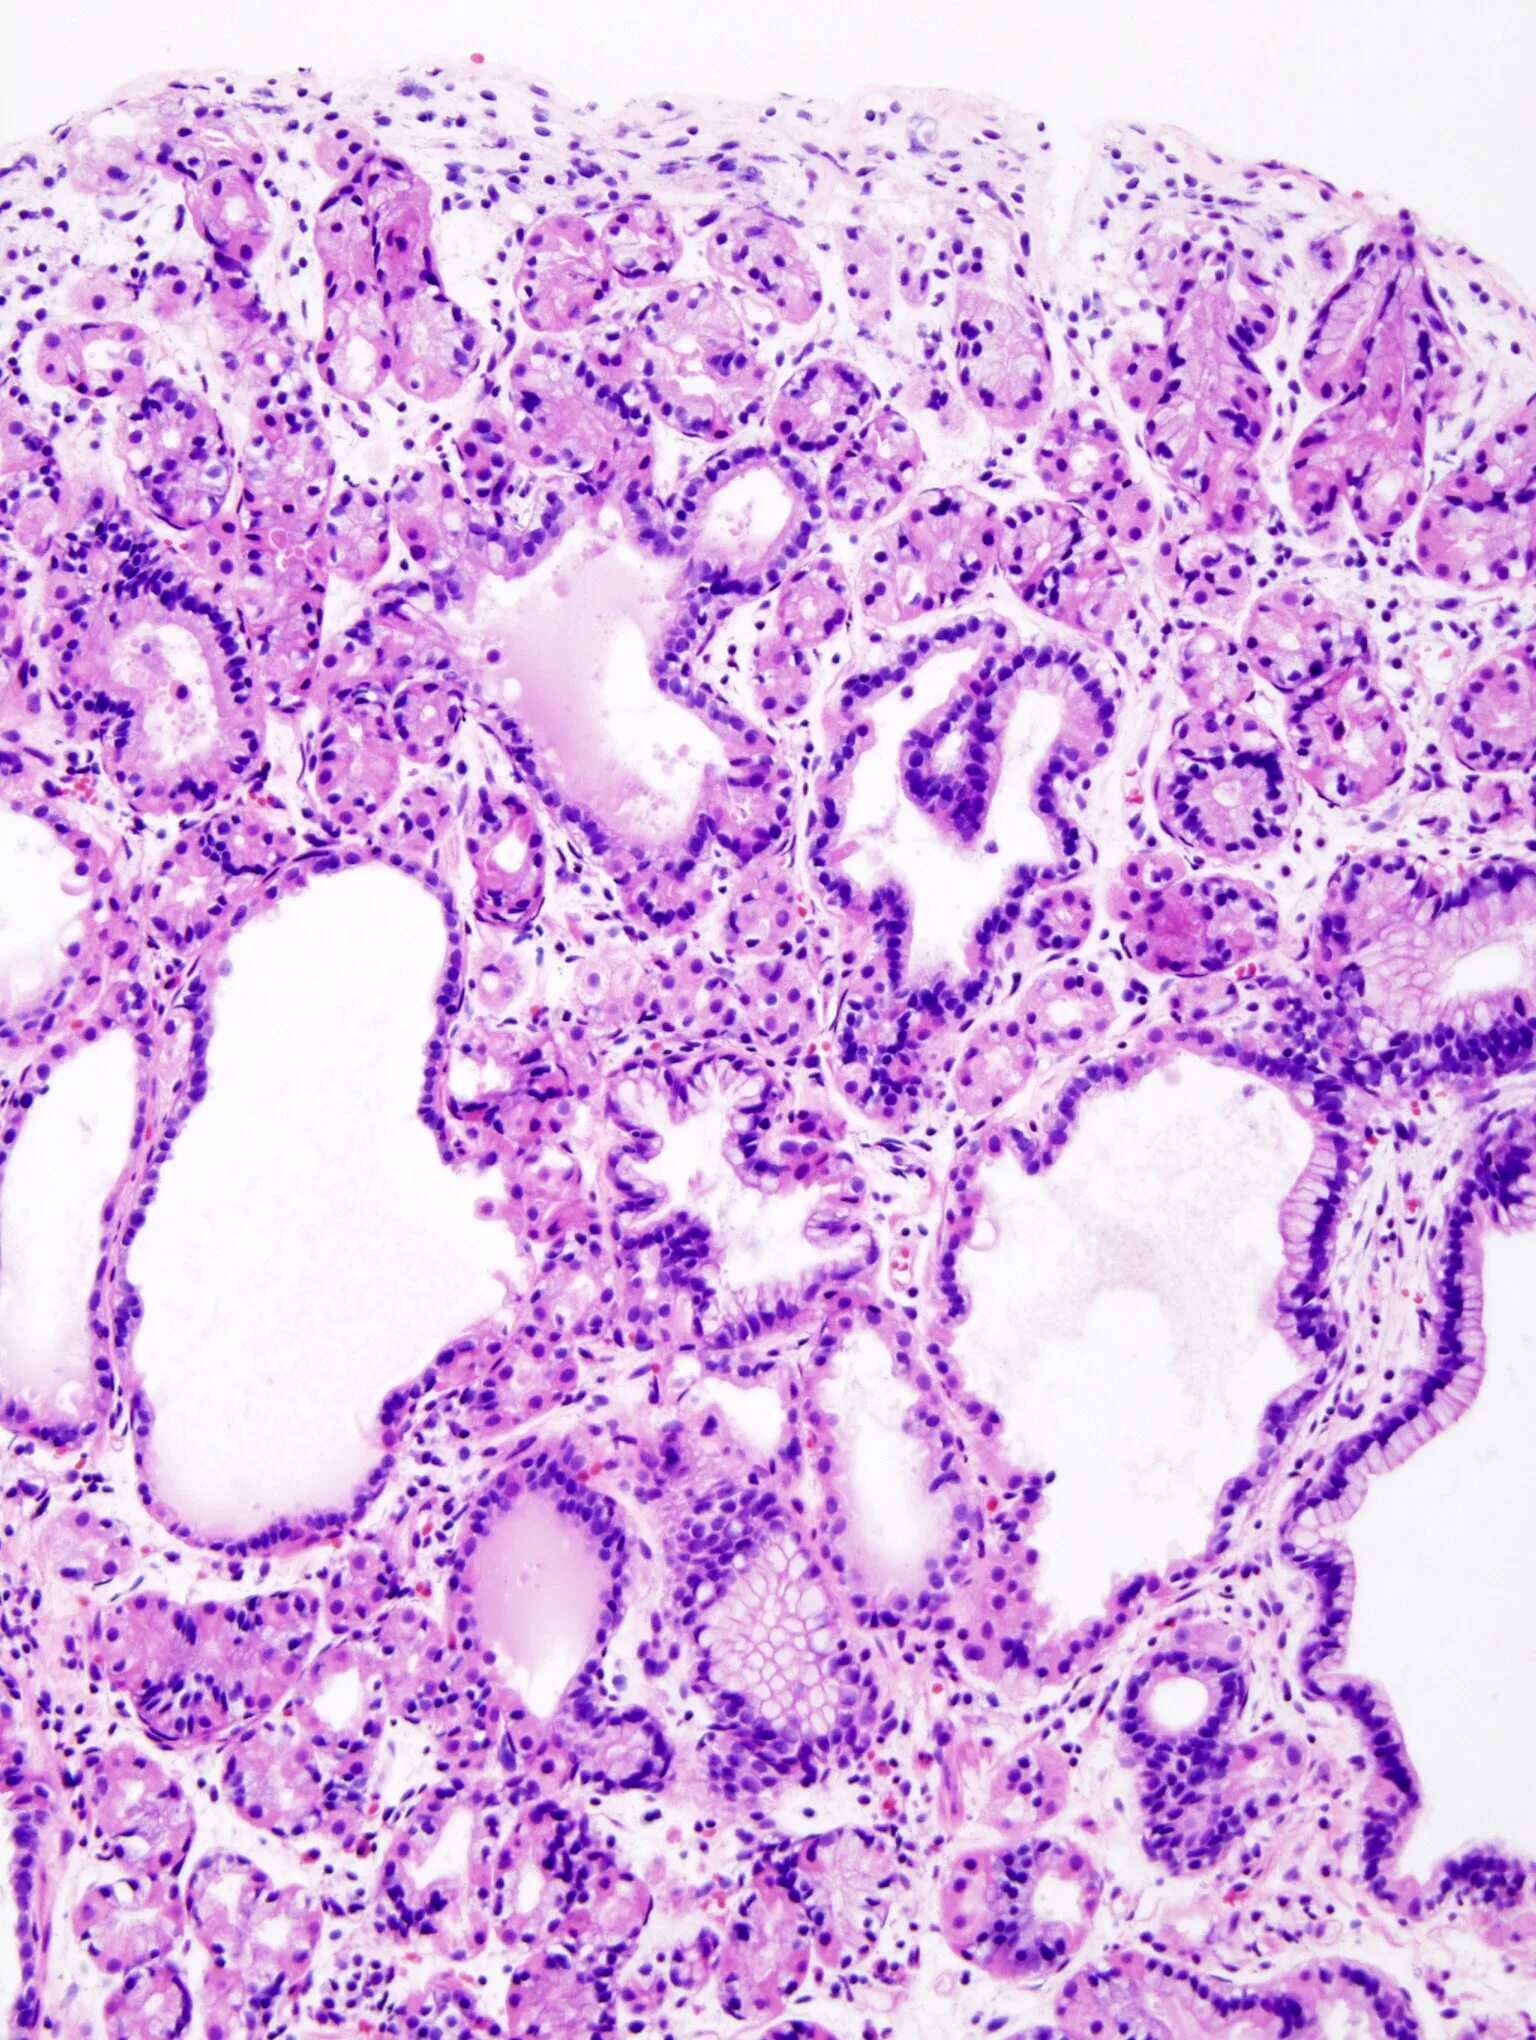

Полип желудка гистология